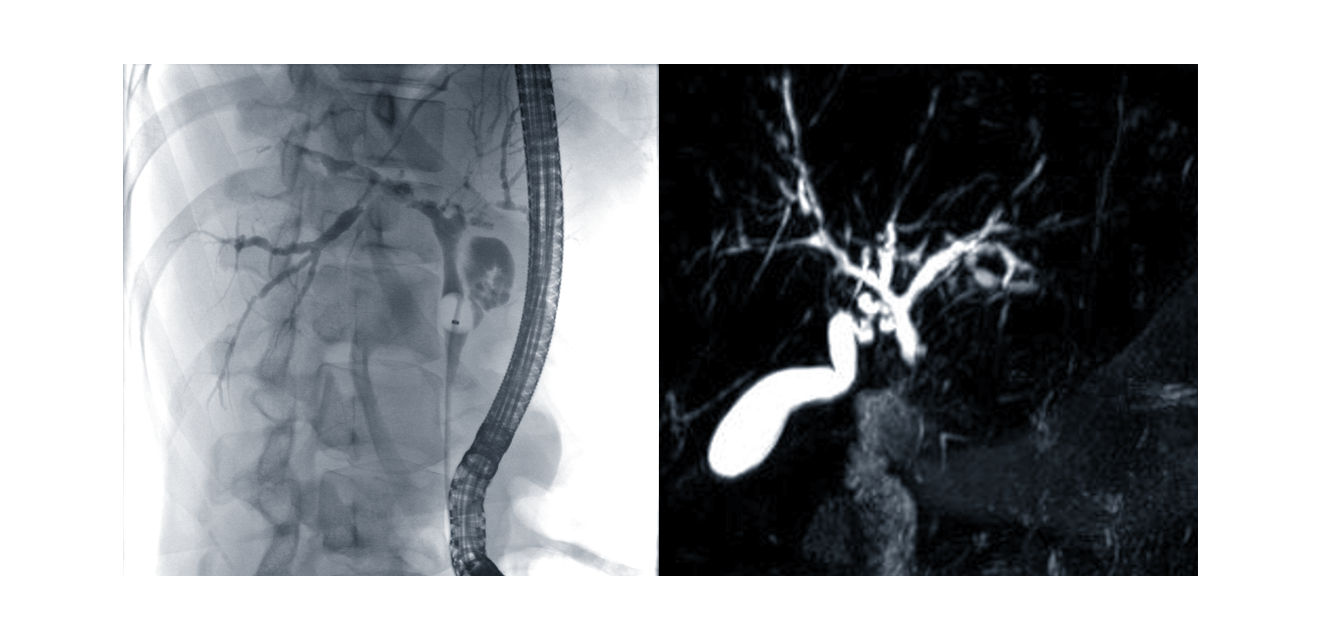

Figure 1. Differential diagnosis of PSC: Diseases of the liver and those affecting the liver, which can lead to features of sclerosing cholangitis. The differential diagnostic considerations in visually apparent sclerosing cholangitis cover a diverse array of conditions apart from PSC. Figure 2. Cholangiogram in PSC: ERC (left image) or MRI / MRCP (right image).

According to current guidelines (European Association for the Study of the Liver 2022, Bowlus 2023) detailed imaging of the extra- and intrahepatic bile ducts by magnetic resonance cholangiography (MRC) is the crucial step in the diagnosis of PSC. The cholangiogram shows the characteristic bile duct changes with multifocal segmental strictures and consecutive dilatations of the intra- and/or extrahepatic bile ducts (Figure 2). Due to the much higher risk potential (especially iatrogenic pancreatitis and cholangitis) endoscopic retrograde cholangiography (ERC) is limited to cases when a therapeutic or diagnostic biliary intervention is indicated. Furthermore, MRI offers the advantage of imaging the hepatic parenchyma and visualising dilated bile duct segments proximal to complete stenoses.